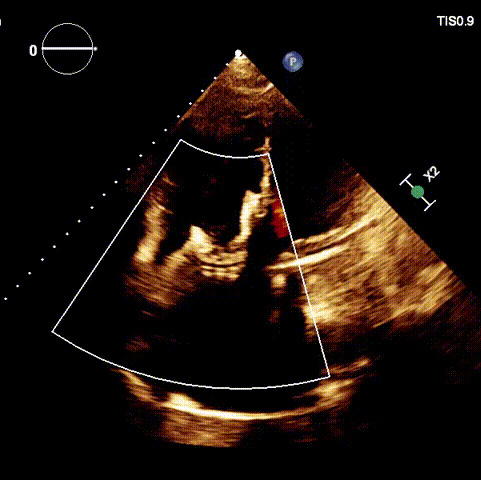

術后超聲

近日,廈門大學心血管病醫(yī)院王焱教授帶領的結構性心臟病團隊,成功應用LuX-Valve Plus經(jīng)血管三尖瓣置換系統(tǒng),為一例高危三尖瓣重度反流患者開展經(jīng)血管三尖瓣置換手術。此次手術系LuX-Valve Plus人工瓣膜在福建省的首例植入,手術過程順利,術后患者三尖瓣反流顯著改善,標志著由葛均波院士團隊作為主要研究者的LuX-Valve Plus經(jīng)血管三尖瓣置換系統(tǒng)全國多中心臨床研究的再一次成功實踐,為三尖瓣介入治療的醫(yī)學循證打下了夯實的基礎。 、